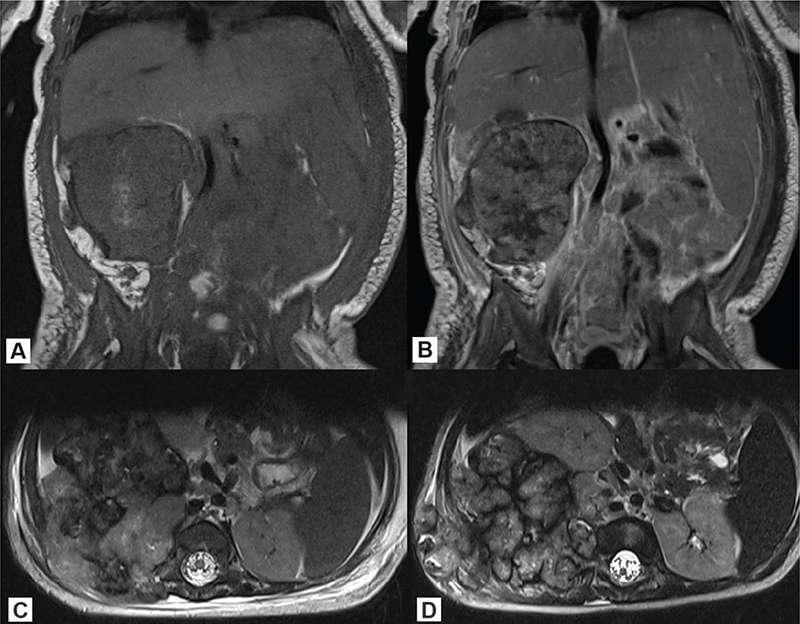

A previously healthy 3-month-old girl was evaluated for a hard and immovable lump lesion on the right lumbar region of her back. An abdomen Computed Tomography (CT) and a lumbosacral Magnetic Resonance Imaging (MRI) were performed and showed a mass of 7.4 × 6.1 × 8.0 cm in the right retroperitoneum with intrusion into the intravertebral foramen Th12-L4 exerting mass effect on the right kidney, liver, and right iliopsoas muscle. According to the Cooperative Weichteilsarkom Studiengruppe (CWS) Guidance 2014 Protocol, the patient was classified to the high risk group, of any histology, N1, IRS Group III, of any initial tumor size. MRI also showed bilateral abdominal and retroperitoneal lymphadenopathy (Figure 1). A biopsy was taken and immunohistochemical staining revealed CD99, FLI1, WT1, BCL-2 and CD31. Moreover, the tumor was partly positive for S-100P, CD56, CD68 and LCA, while negative for chromogranin A, synaptophysin, Myo D1, CD34, calretinin and BCOR. Final histopathological results confirmed the diagnosis of undifferentiated/unclassified small cell sarcoma. The metastatic workup using CT and positron emission tomography (PET) scan did not reveal any distant metastases. The patient received neo-adjuvant CWS-based chemotherapy composed of ifosfamide, vincristine and actinomycin-D. The patient was first treated with 50% chemotherapy dose reduction; however, as the treatment was well tolerated, the doses were escalated to full dose. After the primary tumor regression up to 6.3 × 3.9 × 3.8 cm after the first course of treatment, at 7th week of therapy, a local progression was diagnosed as well as local nodal and distant pulmonary metastases. The patient received the second line chemotherapy based on carboplatin and etoposide, and salvage, off-label therapy with combined irinotecan and temozolomide, but unfortunately the disease progressed despite both therapies. The patient died with malignancy progression a few weeks later.

Figure 1. Lumbosacral MRI of case #1: (A) T1 sequence (coronal), (B) T1 contrast enhanced (coronal), (C) T2 sequence (axial) – at the moment of diagnosis; (D) T2 sequence (axial) at disease progression. MRI: Magnetic Resonance Imaging.